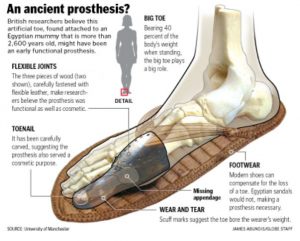

La prothèse la plus ancienne n’est ni une jambe ni un faux œil. C’est un orteil, un gros orteil appartenant à une noble Égyptienne vivant il y a environ 3000 ans.

Aujourd’hui, cela peut sembler étrange, car une personne peut bien vivre sans son gros orteil. Mais pour la société égyptienne, le gros orteil était d’une prime importance, car le port de sandales était de coutume, et suffisamment important pour justifier la construction de cette prothèse précoce.

Et de surplus, l’orteil était fabriqué de manière «éthique». Le matériau, la conception et même les articulations qui imitent la flexion des articulations métatarsophalangiennes pour éviter le frottement de l’os naviculaire font référence au confort et à la tolérance de l’orteil prothétique du porteur.

L’esthétique de la conception prothétique n’a pas non plus été négligée. Ces caractéristiques sont éthiquement essentielles pour réhabiliter le patient, en particulier après les amputations.

Se pose aussi la question de savoir si l’orteil était un marqueur de l’équité entre hommes et femmes? Toutes les hypothèses sont permises.

Il semble que ce soit autant une question d’identité que de fonction. L’orteil trouvé a été conçu pour une femme, ce qui signifie que la technologie prothétique proposée avait réussi à supprimer les disparités de santé entre les hommes et les femmes.

Le Dr Jacky Finch de l’université de Manchester a déclaré que

«Les données sur la pression nous disent qu’il aurait été très difficile pour un Égyptien ancien qui manquait un gros orteil de marcher normalement avec des sandales traditionnelles. Ils pouvaient bien sûr rester pieds nus ou avoir peut-être porté une sorte de chaussette ou de botte sur le faux orteil, mais nos recherches suggèrent que le port de ces faux orteils rendait la marche en sandale plus confortable.»